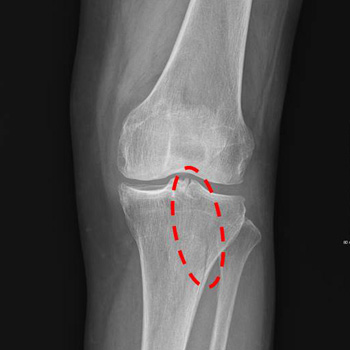

On October, 13 of 2024, I was on a pedestrian crossing and as the traffic light was changing to red, I hurried to run and missed my step. After slipping down, I ached severely in my left knee and had a difficulty walking properly. I narrowly came back home with the aid of those around me. In the morning of next day, I called my great parish pastor Geumran Hwang and she prayed for me over the phone. After that my pain was relieved and I went to the hospital for the examination. Through the X-ray result, the doctor said to me, “You have the left patella fracture, and need a surgery.” But I didn’t receive surgery and returned home wearing a cast. I thought over why this happened to me and looked back on my past days. And I repented of my hot-temper, ill-feelings, envy, judgment, condemnation, and of not praying fervently. Afterwards whenever I attended Sunday morning services, I received Senior Pastor Soojin Lee’s prayer for the sick. On October 29, Chinese Parishes 2 & 3 held a special prayer meeting for the fullness of the Spirit and I took a taxi with the help of my husband and my district leader to attend it. Speaker Pastor Miyoung Lee prayed for me and the fire of the Spirit came upon me. I felt like my head, waist, and legs became hot and refreshed. One the way back home after the meeting, there was no pain and I could step down on the ground with my left foot. I wanted to be healed completely and examined my life reading a religious book ‘The Message of the Cross.” I repented of my detailed wrongdoings such as not performing my missions sincerely. On November 1, I attended a Friday night service happily and then dreamed of Senior Pastor Soojin Lee. In my dream, she said to me, “Rise up and walk!” I woke up and became assured of my healing. Later I took off a cast and tried moving my leg. I was able to walk well without a cane I had leaned on. Hallelujah! In addition, I had felt a lump, the size of a cherry tomato, in the left neck from two years ago and in the morning one day I found it had also disappeared. I wanted to make it sure medically, and went to the hospital for the medical examination on November 14. The doctor said, “A patient with patella fracture cannot move their legs even after one month. It’s a miracle that you are able to move your leg just in three weeks even without surgery.” And he added, “Your fracture is completely restored, too!” Hallelujah! I give all my thanks and glory to Father God who healed me of patella fracture at the risk of surgery.

X-ray result

▲ Before prayer: patella fracture with articular surface